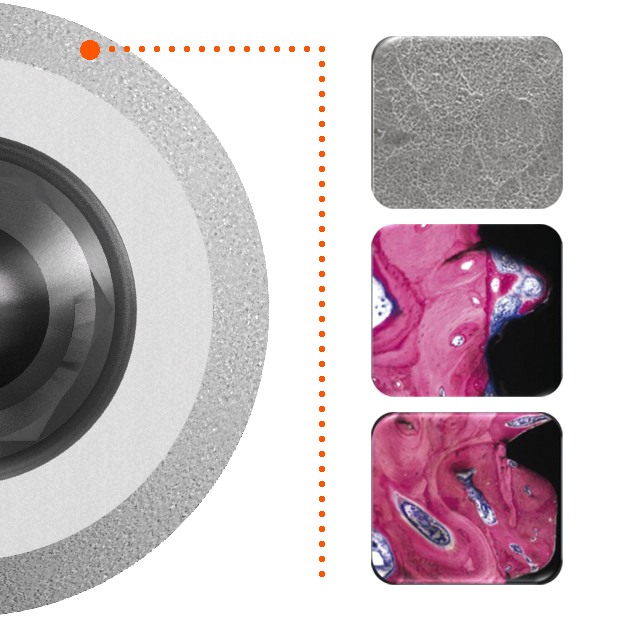

Immédiatement visibles lors du sourire, les restaurations à visée esthétique constituent un défi majeur car elles doivent prendre en compte non seulement les tissus dentaires environnants (émail et dentine), mais aussi les tissus parodontaux (os et gencive) dont la prévisibilité peut être très relative. Le défi esthétique est d’autant plus complexe que le succès de ce type de restauration est soumis à la subjectivité du patient. Néanmoins, la reconstruction des papilles, l’alignement des collets, le choix des bons matériaux et le maintien de la santé parodontale sont autant de critères universels à prendre en compte afin d’évaluer la reproductibilité et la pérennité des techniques opératoires mises en œuvre.